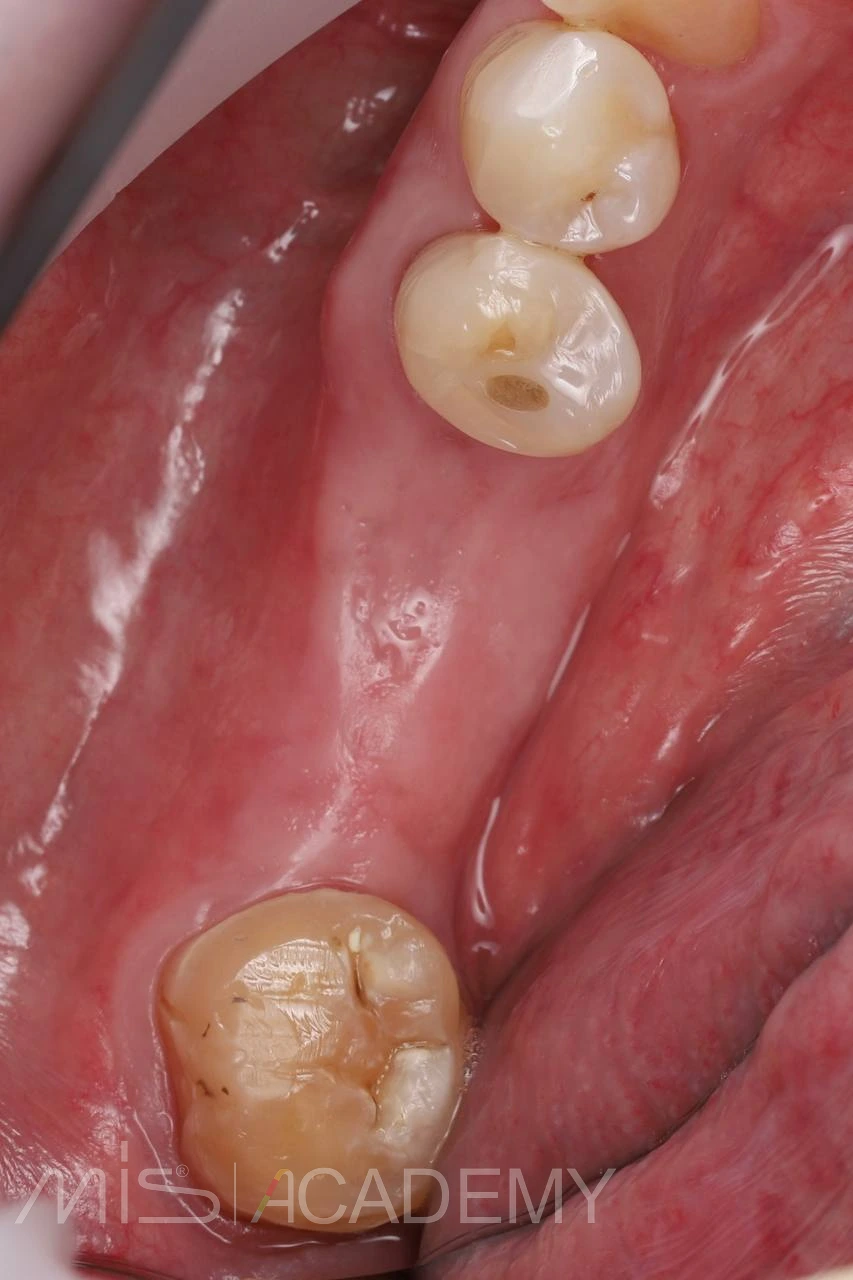

Устранение включенного дефекта зубного ряда на нижней челюсти, который в ходе лечения стал концевым.

— Имплантация 4.6, 4.7 MIS C1.

— Профилирование кости.

— Трансплантат с бугра под вестибулярный лоскут.

— Удаление зуба 4.8 после остеоинтеграции имплантов.

— Искусственные коронки из диоксида циркония на зуб 4.5 и импланты 4.6, 4.7 (2 месяца после фиксации).